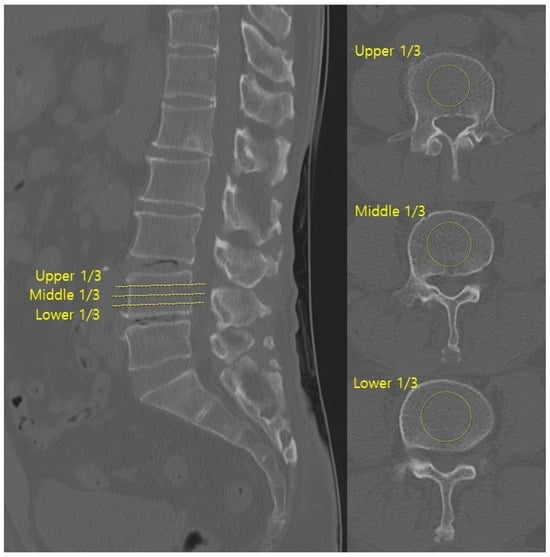

HU values were measured on axial CT images at three levels (upper, middle, and lower thirds) of both the superior and inferior vertebrae body adjacent to the surgical disc space (Figure 1). Regions of interest (ROIs) were placed centrally in the trabecular bone, avoiding cortical margins and venous channels. The centre of each ROI was targeted to the central portion of the vertebral body, and the ROI area was set to include more than 50% of the vertebral body cross-sectional area while avoiding inclusion of the cortical bone.

Metal artefacts from posterior instrumentation were carefully avoided during ROI placement. All CT images were acquired with a slice thickness of 1–3 mm. The mean of three measurements for each vertebra was calculated, and the final HU value per surgical level was the average of the superior and inferior values [17]. CT scans were obtained using a multidetector CT scanner (Ingenuity, Philips Healthcare, Eindhoven, The Netherlands).

Sagittal parameters were assessed using preoperative and postoperative lateral lumbar radiographs (Figure 3). The parameters were anterior disc height (ADH), posterior disc height (PDH), foraminal height (FH), segmental lordotic angle (SLA), and lumbar lordotic angle (LLA). ADH and PDH were defined as the vertical distances between the superior and inferior endplates at the anterior and posterior margins of the surgical level, respectively. FH was the maximum vertical distance between the inferior pedicle of the upper vertebra and the superior pedicle of the lower vertebra. SLA was the Cobb angle between the superior endplate of the upper vertebra and the inferior endplate of the lower vertebra at the surgical level. LLA was the Cobb angle from the superior endplate of L1 to the superior endplate of S1. Postoperative cage position was categorized as anterior one-third (anterior group) or middle one-third (middle group) of the inferior endplate [3]. All measurements were performed using PACS workstation software (INFINITT G3, INFINITT Health care, Seoul, Republic of Korea).

Figure 3. Sagittal parameters of ADH, PDH, FH, SLA, and LLA were measured on lateral radiographs, and cage position was categorized as anterior or middle based on its location on the inferior endplate.